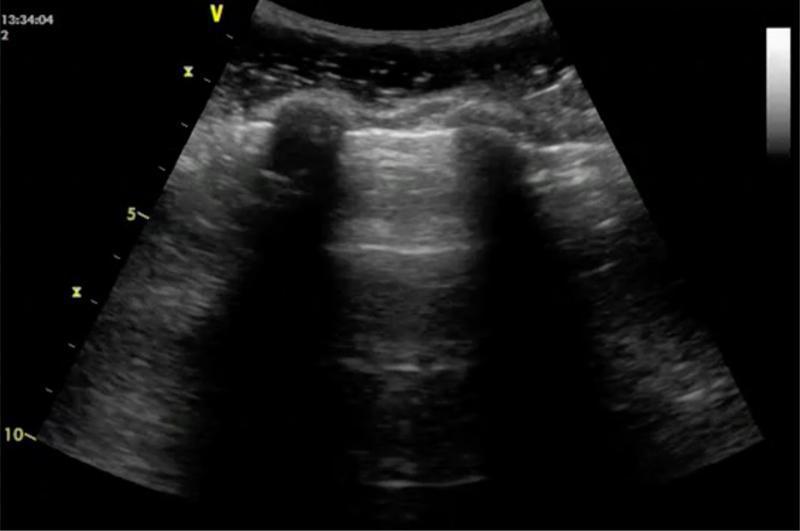

- Lignes A : artefacts horizontaux parallèles, équidistants, répétés sous la plèvre.

Les lignes A sont des réverbérations horizontales répétées, parallèles à la plèvre.

Elles s’estompent progressivement avec la profondeur.

Origine – Ces artefacts sont dus à la réflexion répétée des ultrasons entre la plèvre et la sonde, à l’interface air–tissu.

Interprétation – La présence de lignes A indique un poumon bien aéré, sans surcharge interstitielle ni condensation.

Lignes A + glissement pleural. © POCUS Atlas